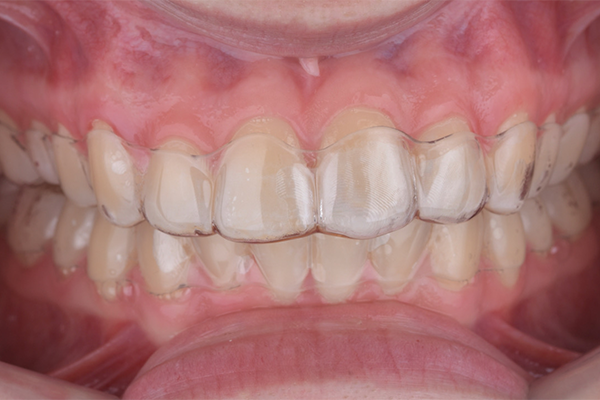

Considerando que a paciente havia finalizado recentemente o tratamento ortodôntico com alinhadores invisíveis, foram utilizadas as placas de acetato confeccionadas para contenção dos arcos como moldeiras personalizadas para o clareamento caseiro. A paciente foi orientada a aplicar uma pequena quantidade de gel (uma gota) na região mais profunda da placa, correspondente aos dentes envolvidos no clareamento em consultório, utilizando-as por 3 horas diárias durante o intervalo entre as sessões clínicas.

6 | Utilização das contenções como placas personalizadas de clareamento.